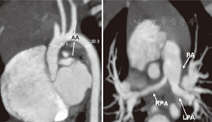

心脏彩超示右心房、右心室内径增大,右心室前壁明显增厚,左、右肺动脉发育细小(图1),主肺动脉发育尚可,肺动脉瓣无明显增厚,开放正常,房间隔中部探及回声中断约0.81 cm,缺损周围可探及房间隔结构回声,室间隔连续完好。CT动脉造影检查示主肺动脉发育可(10.9 mm),双肺动脉狭窄,左肺动脉宽约4.3 mm,右肺动脉宽约2.8 mm。主动脉显示较细,主动脉起始部、弓部、降部分别宽约6.7 mm、4.3 mm、4.3 mm (图2)。头颅磁共振成像示脑外腔隙增宽,髓鞘化落后于月龄。Gesell发育测试:动作发育商60分,应物发育商51分,言语发育商32分,应人发育商34分。

注:AA:主动脉弓部;PA:主肺动脉;RPA:右肺动脉;LPA:左肺动脉 AA:aortic arch;PA:pulmonary artery;RPA:right pulmonary artery;LPA:left pulmonary artery